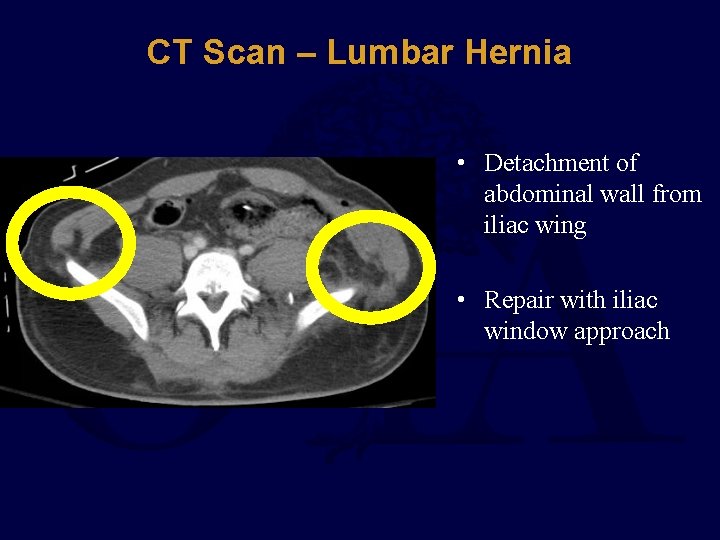

CT Scan – Lumbar Hernia • Detachment of abdominal wall from iliac wing • Repair with iliac window approach